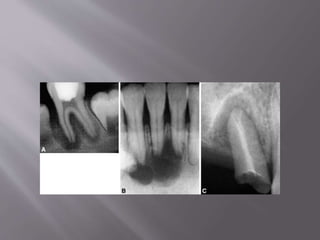

 Pressure resorption due

to orthodontic

treatment. A. Teeth at

the start of orthodontic

treatment. B. Severe

root resorption on the

left central incisor after

orthodontic treatment.

Note that, even though

considerable resorption

has taken place,

favorable healing at the

apex with cementum

can be seen. (Courtesy

Dr IB Bender)